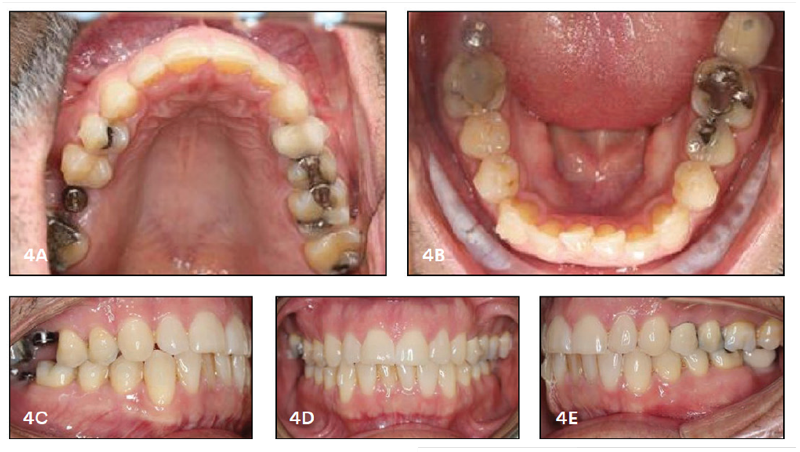

Fig. 4: Four months into treatment.

We then gave the patient 13 aligner trays to be used over the course of the next few months (Fig. 4, pg. 37). Once the implants were placed, we trimmed the tray slightly to make sure that it wasn’t placing any pressure on the implant. Otherwise, we didn’t need to make any further adjustments with the aligners.